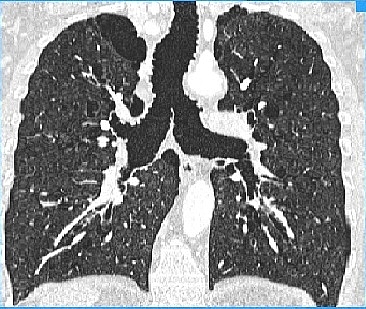

ESTUDO DO EFEITO DO CPAP NA SÍNDROME DE MOUNIER-KUHN: ENCAMINHE SEU PACIENTE.A Divisão de Pneumologia do InCor HCFMUSP está realizando um estudo sobre a presença de colapso da via aérea em portadores de Síndrome de Mounier-Kuhn. A proposta é diagnosticar e registrar o colapso por broncoscopia e avaliar o efeito do CPAP sobre o mesmo. Para isso o grupo está recrutando pacientes com a síndrome para inserir no projeto. Caso você acompanhe algum paciente com Síndrome de Mounier-Kuhn e quiser colaborar encaminhando esse paciente, entre em contato com a Dra. Evelise Lima pelo email projetosmk2017@gmail.com.

Para ler mais sobre a Síndrome de Mounier-Kuhn no PneumoImagem, clique aqui.